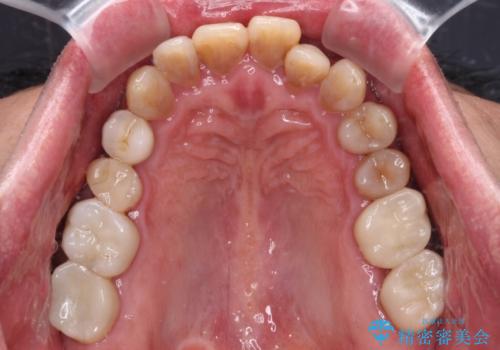

- 前歯のクロスバイトを気にして来院された患者様です。

40代男性で、インプラント補綴治療も経験されている方で、矯正治療をしても良いのかと悩んでいらっしゃいました。

下顎骨の左右のずれがあり、下顎全体が前方に出ている状態であったので、無理をせずにワイヤー装置にて矯正治療を行うこととしました。

クロスバイト改善には難儀しましたが、咬みやすく、笑ったときに清潔感ある口元に仕上げることができました。